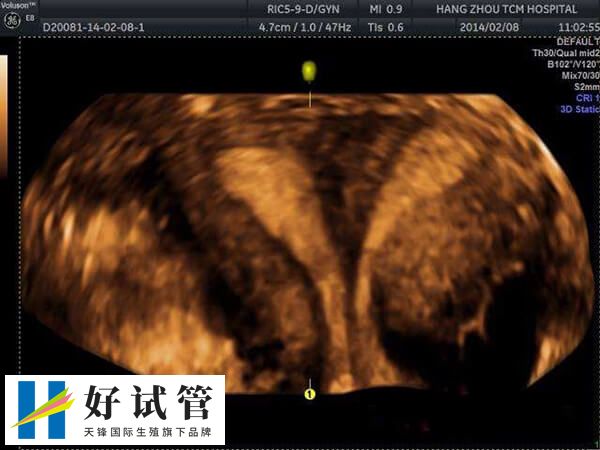

一般龙凤双胞胎参与性别选择,而因中国明令禁止通过试管技术进行非医学需要的胎儿性别鉴定,所以试管移植选龙凤胎是随机的,其费用也与普通试管婴儿并无差异,具体费用明细如下所示: